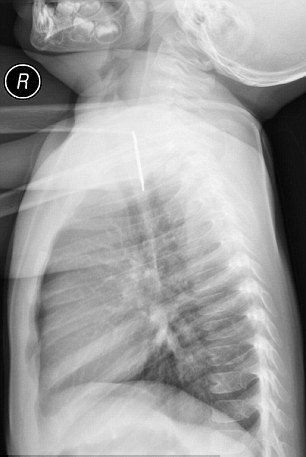

صراط: پزشکان در کشور عربستان سعودی از مشاهده تصویر یک عروسک که داخل مری یک کودک 16 ماهه گیر کرده بود شوکه شدهاند.

گفتنی است: این کودک نوپای 16 ماهه آویز گردبند خواهر خود را بلعیده بود و دچار علائمی مانند تنگی نفس و مشکل در بلع شده بود.

بررسیها نشان میدهند، پزشکان در ابتدا پی نبرده بودند که چه مشکلی برای این کودک پیش آمده است و با انجام عکسبرداری اشعه ایکس موفق به ردپای این شی در مری او شدهاند.

نکتهی منحصر به فرد در این حادثه بدست آمدن یک تصویر کاملا واضح از گردن آویز است به طور که حتی جزئیات آن نیز قابل مشاهده است و کارشناسان این پدیده را شگفت انگیز در دنیای تصویر برداری اشعهX ذکر کردهاند.